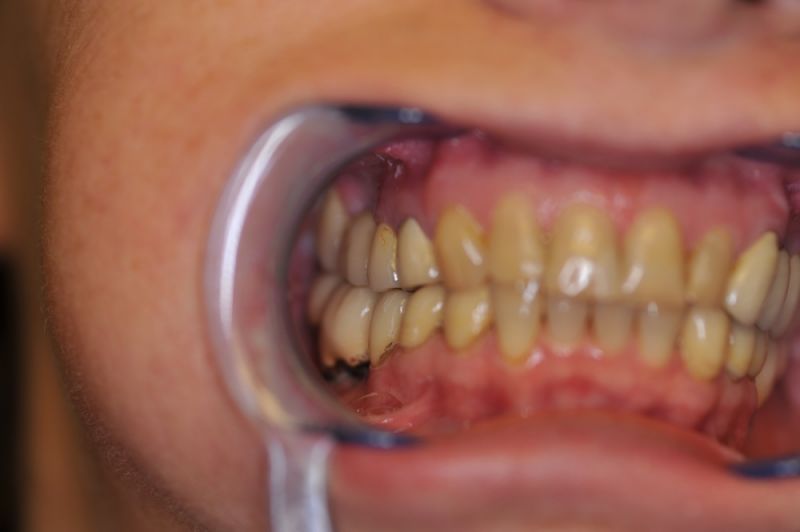

Es war eine Kombination aus Schmerzen bis an die Suizidgrenze, beschränkten wirtschaftlichen Möglichkeiten, sehr stark eingeschränkten Möglichkeiten der für Implantate zur Verfügung stehenden Knochenverhältnisse in einem stark atrophierten Unterkieferseitenzahnbereich und zudem dann auch noch durch auftretenden Problemen bei der Implantatinsertion und nachfolgenden Versorgung der Implantate.

Die Problematik der Implantatversorgungen kann man in einer Analogie folgendermaßen darstellen. Die räumlich beengten Zustände gleichen dem Tanz eines Paares auf einer Briefmarke, und der gleichzeitigen Schritt- und Fusshaltung, dass beim Tanzen die Schuhe geputzt werden können!